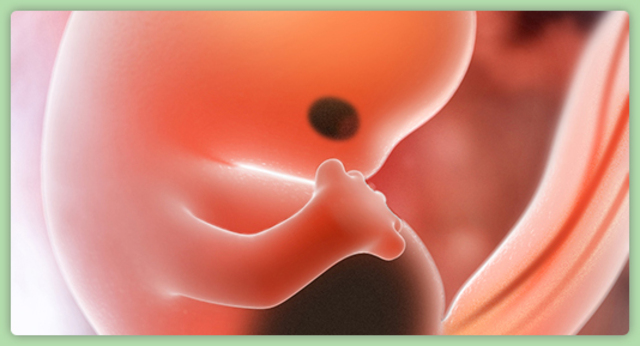

Month Two

Size at the end of this month should be around 1 and 1/8 of an inch. In boys, gender also starts to become visually distinguishable.

• Arm and Leg Buds Form

Arm and Leg Buds Form

• Back Begins to Straighten Out from the C-Shape

Back Begins to Straighten Out from the C-Shape

• Bones Are Developing

Bones Are Developing

• Fingers and Toes are Visible, but Webbed

Fingers and Toes are Visible, but Webbed

Lungs are mostly developed but still not functioning yet.